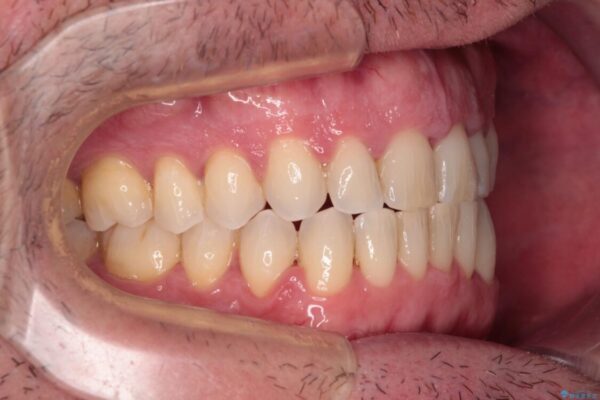

治療後

• 前歯でものを噛みきりたい 目立たない装置でのワイヤー矯正 治療後画像